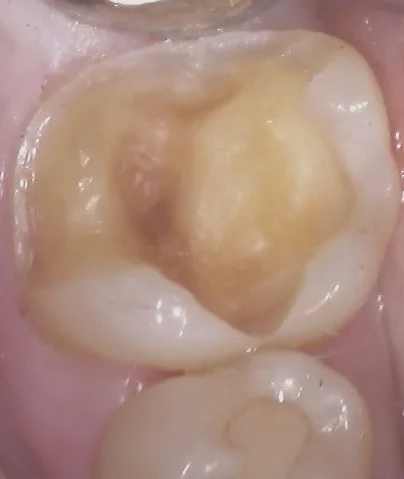

処置前の写真がこちらです。

上の金属部分が今回の治療箇所です。

・・・なんか、トリミングしたらズームになって無茶苦茶歯のサイズが大きいですね・・・。

まぁ細かい形状とかも分かりやすいかもなので、良いですけども・・・。

で、金属部分の下に虫歯があるのがレントゲン上でも強い光を通して判断する方法(透照診)でも明白だったので、治療介入しました。